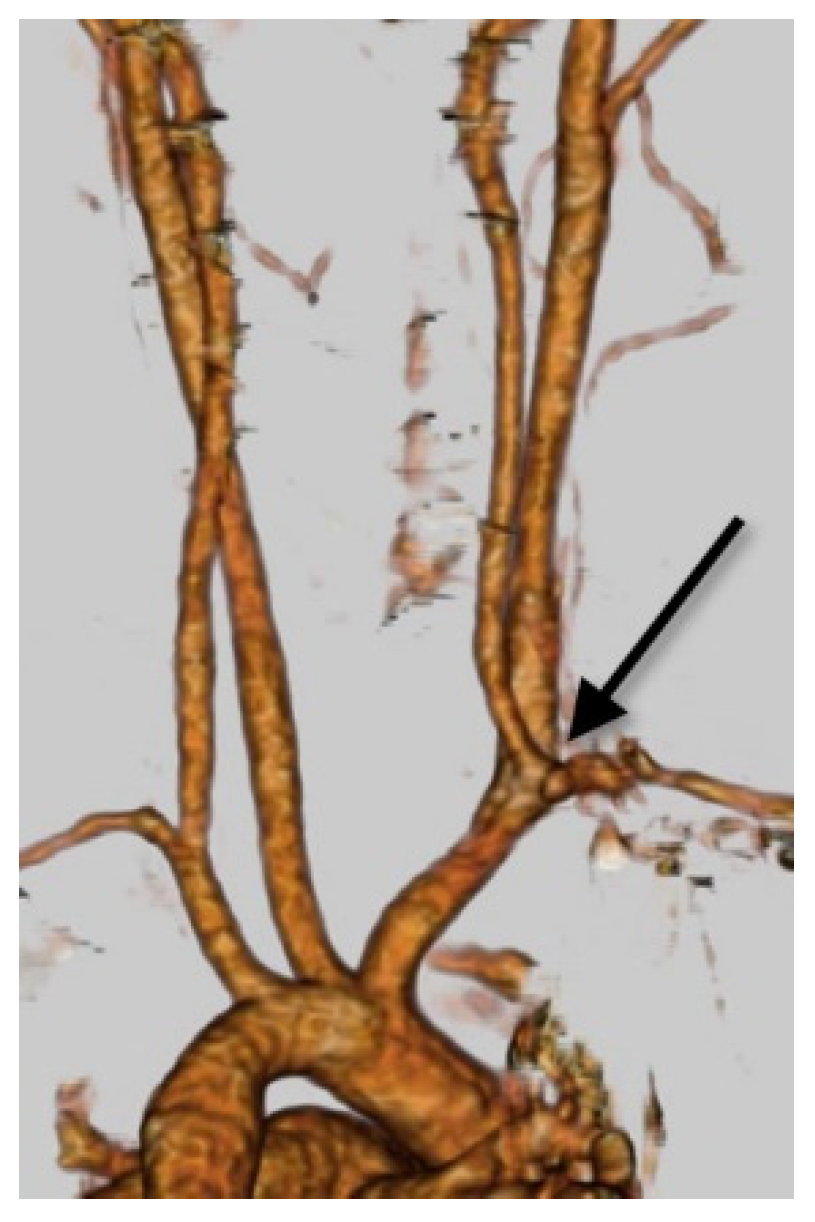

Figure 6.

Right VA originating from the BCT. Right posterior oblique view on VR-CT angiography shows the RVA arising from the BCT (black long arrow). The SYNAPSE VINCENT software 6.3 (Fujifilm Holdings Corp., Tokyo, Japan) was used to obtain the VR image.